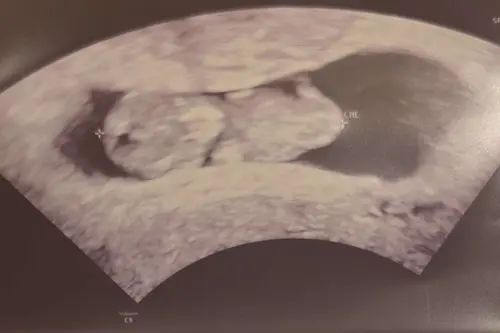

Ik had een T- vormige baarmoeder (aangeboren afwijking), waardoor ik niet zwanger geraakte. Ik kreeg een kleine ingreep en ben nu 11 weken zwanger. Vermits je aangeeft dat je al een 1e mooie zwangerschap doormaakte, zou ik er vanuit gaan dat je baarmoeder nu ook wel mooi zal meegroeien met je kindje 馃檹 Je bent toch al 11 weken ver, dus de kans op verlies wordt nog steeds kleiner en kleiner

Hier ook eerste zwangerschap met hartvormige baarmoeder zonder problemen kunnen volbrengen. Nu ook 12w van het tweede. Zou me geen zorgen maken indien alles goed lijkt te gaan op de echo!